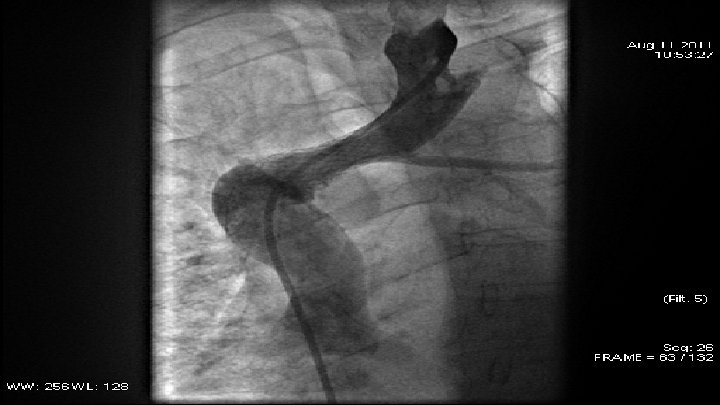

Case 2 q 59 y. o. patient q June 2011 - diagnosed with small-cell lung cancer q August 2011 - angiographic data of subtotal occlusion of VCS. q. PTA – baloon dilatation and stent implantation